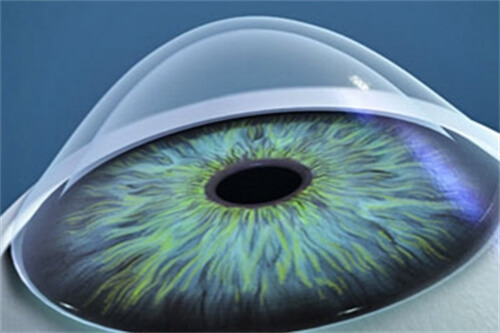

人工晶体植入术(ICL)通过在眼内植入一个特殊的人工晶体来矫正视力,这种手术避免了切削角膜的风险,且对角膜厚度没有严格要求。对于近视度数高达1500度的患者来说,这种手术方式可能更为适合。ICL手术适应的近视度数范围广泛,通常可矫正300度到2300度的近视,以及600度以下的散光。